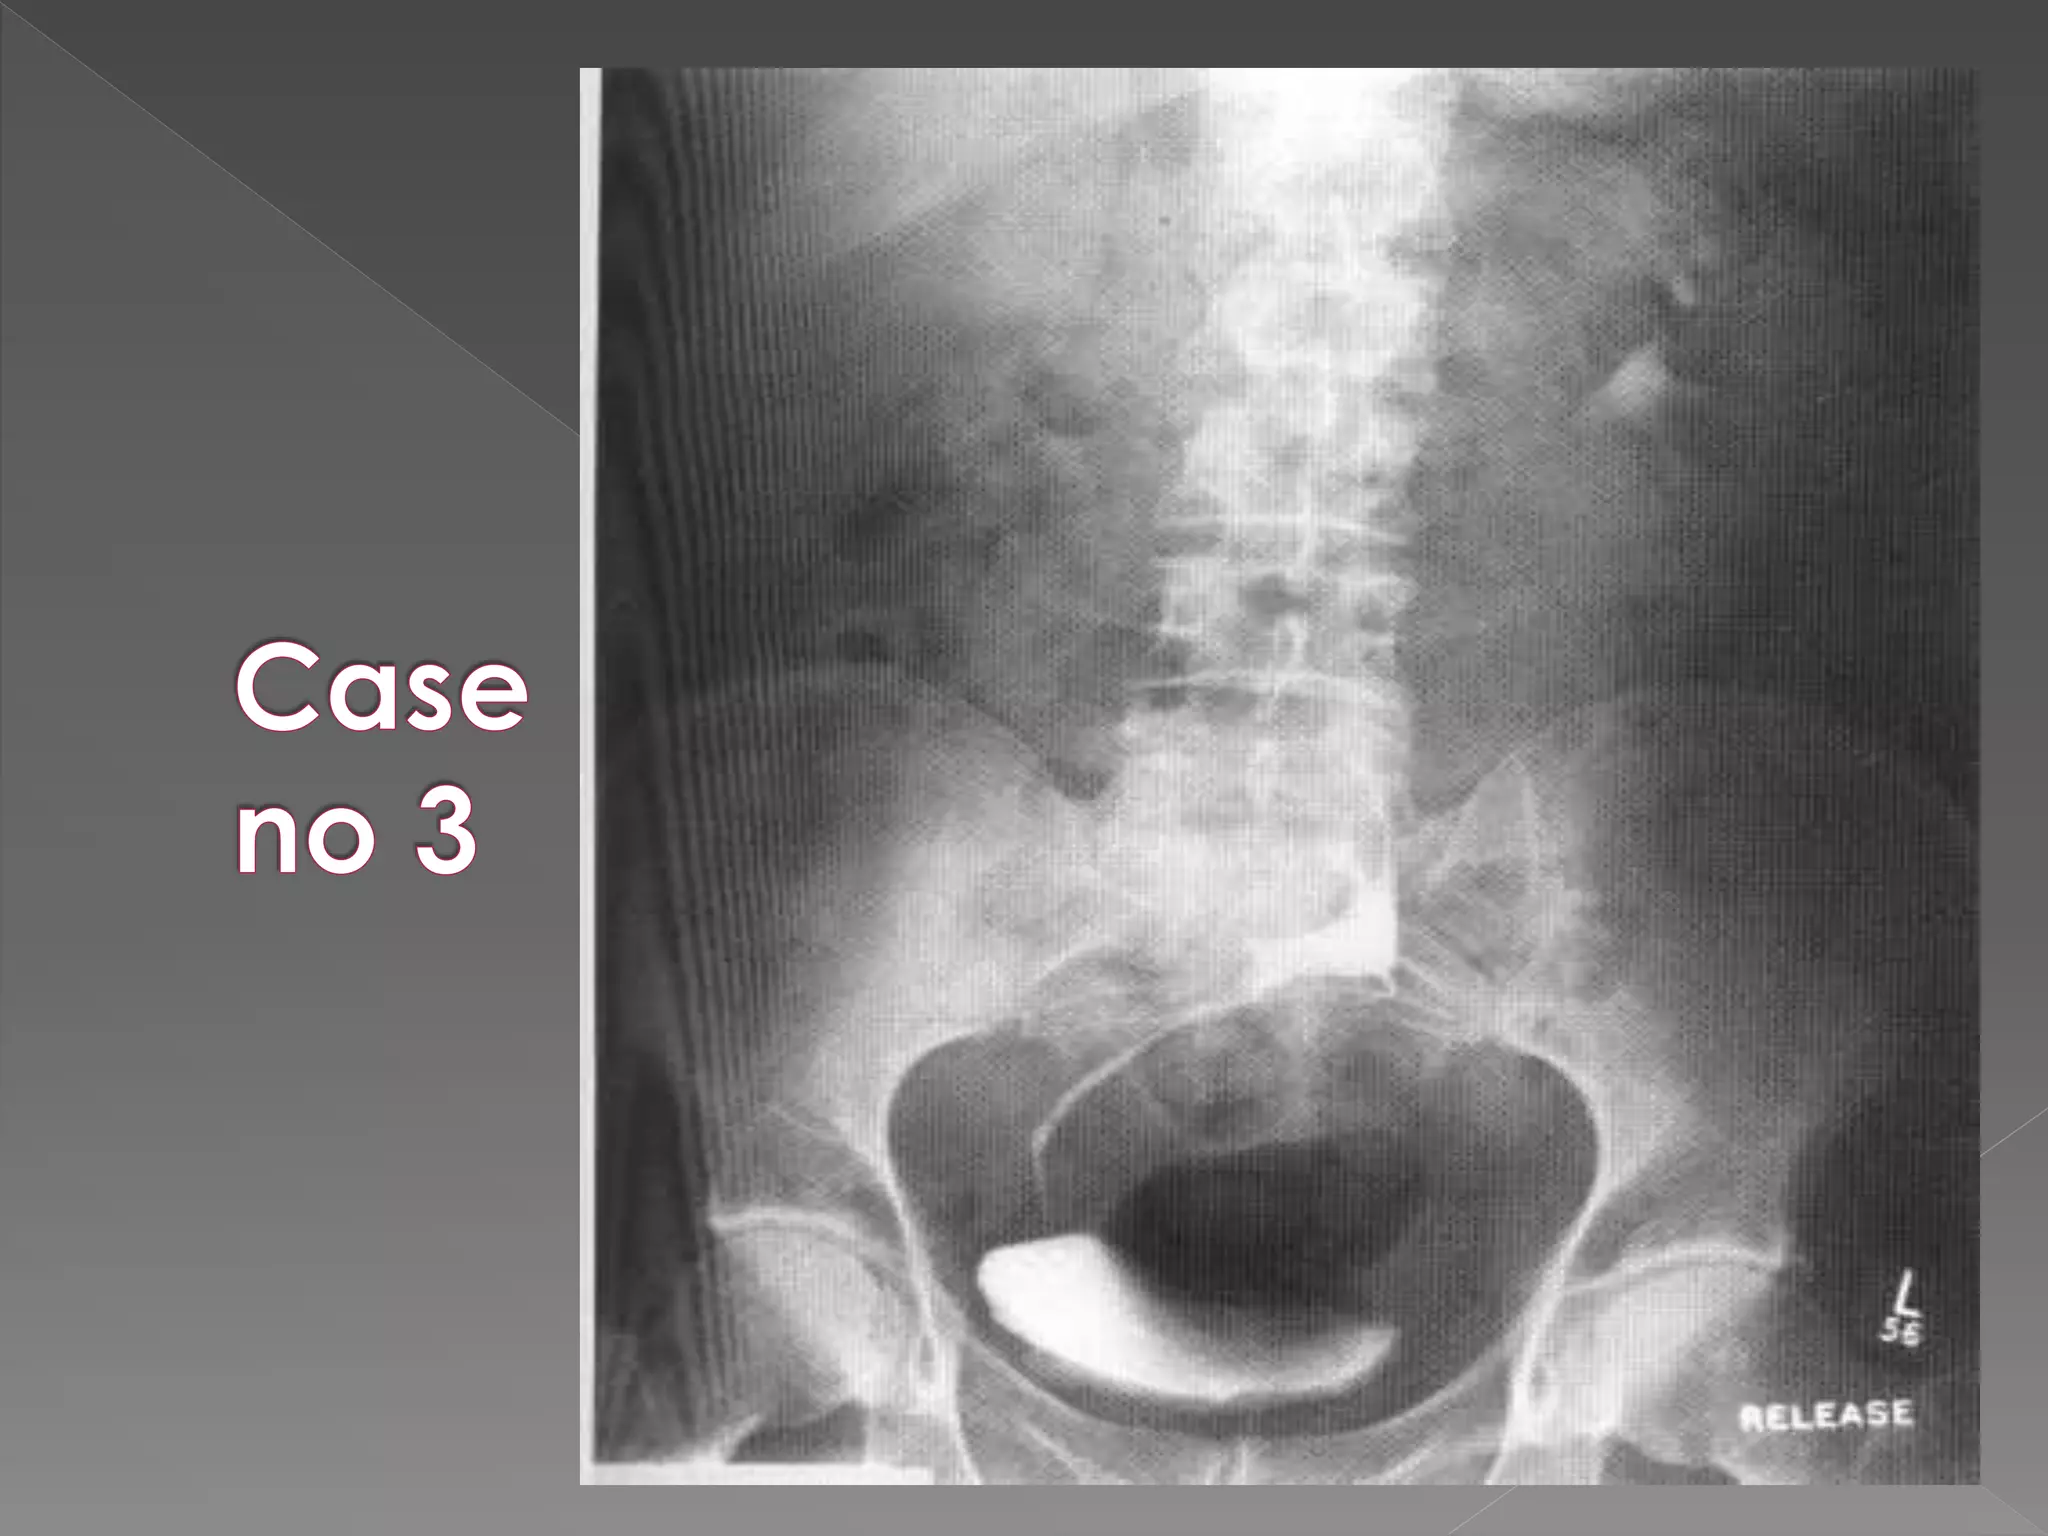

5) Immediately after release of

compression full length film. (full length)

 On releasing compression increase flow in

ureters making them prominent in post

release film.